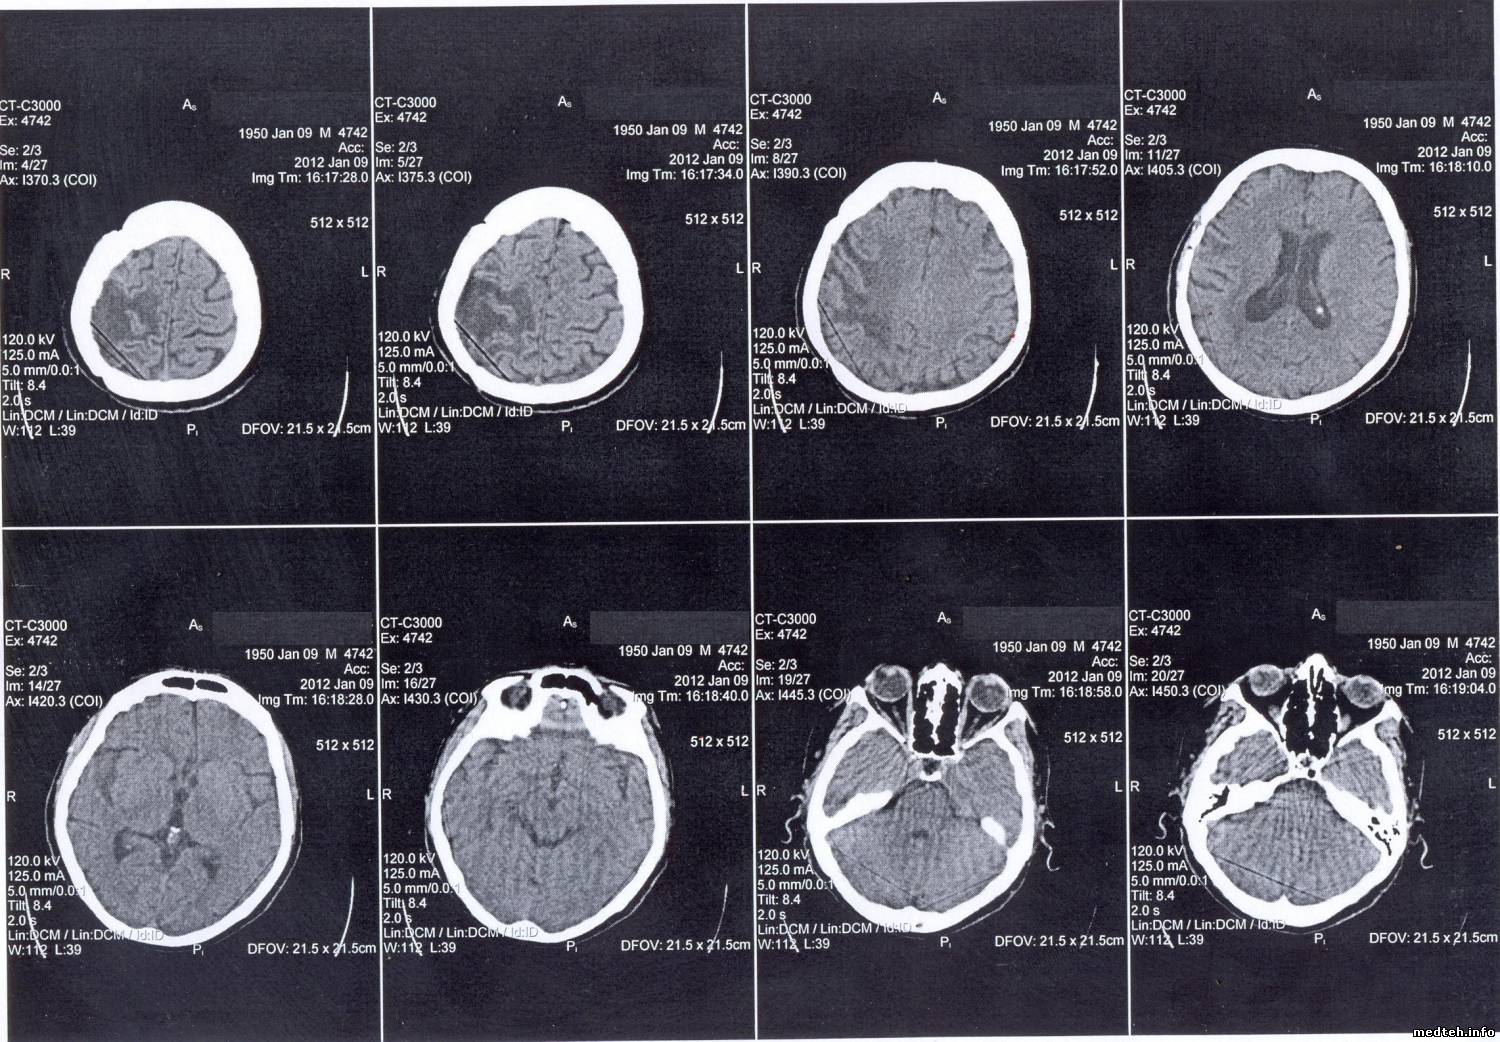

3. Кольцевые круги. Врачи говорят, что зависит от температуры в помещении, где установлен томограф (там стоит мощная сплит-система), При 25 есть, при 21 градусе исчезает. По словам врачей, лечилось это раньше калибровкой по фантому. Пока ее не делал. Не совсем понимаю, как это связано с температурой.